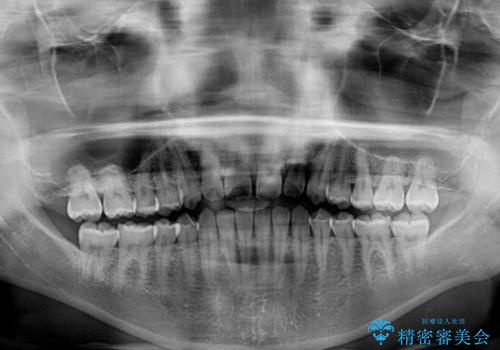

- 後戻りによる上下前歯の隙間を気にして来院された患者様です。

歯列不正はそれほど大きくなかったため、インビザライン・ライトを用いて矯正治療を行うこととしました。

無理のないペースで治療を進め、9ヶ月で終えることができました。